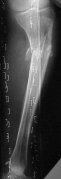

Молодой женщине по поводу бамперного перелома через 2 недели после травмы выполнен остеосинтез большеберцовой кости гвоздем ChM в одной из больниц Москвы. Снимок приложен. Сейчас речь пошла об удалении гвоздя и остеосинтезе пластиной. Действительно ли это оптимальный план? Какие есть еще варианты?

A female 24 years old, a sister of a friend of mine (not physician) living in Moscow, 3 weeks ago admitted to the hospital in Moscow after a car accident (was a pedestrian) with a tibial shaft fracture. 3 days ago closed locked nailing was performed, see attached films. Now he is in panic because they are going to remove the nail and perform plating.

The tibia shaft fracture (proximal 1/3 of the shaft) is apex medial 20 degrees, slightly short and a few degrees apex anterior after nailing. The nail extends quite proximal to the entry site. I wasn't able to see the distal end of the nail on my screen and am not certain if there was distal locking.